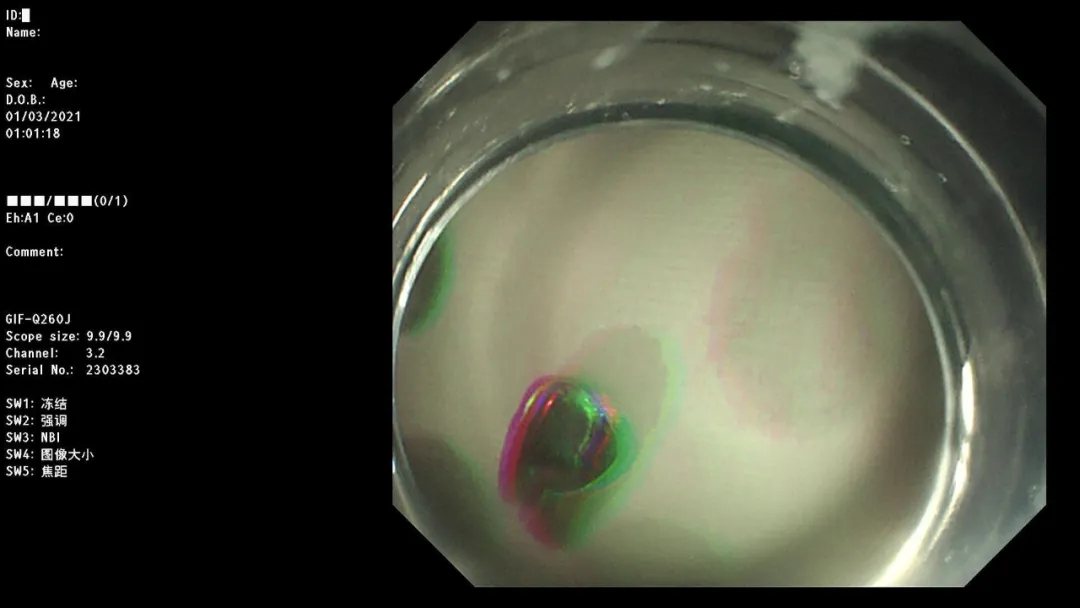

急诊胃镜示:十二指肠降段活动性渗血,予钛夹夹闭,检查诊断:十二指肠降段多发血管畸形并出血急诊钛夹止血术。